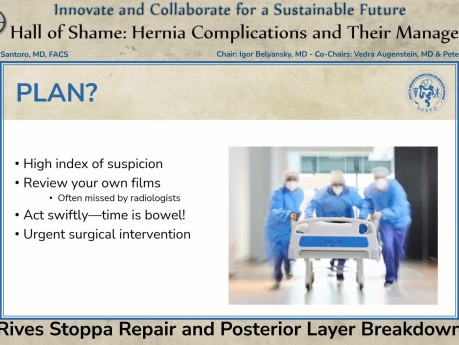

Reparación de Rives Stoppa y ruptura de la capa...

Presentación quirúrgica: Reparación de Rives Stoppa y ruptura de la capa posterior, presentada en la sesión "Salón de la Vergüenza: Complicaciones de la Hernia y su Manejo" por Peter Santoro...